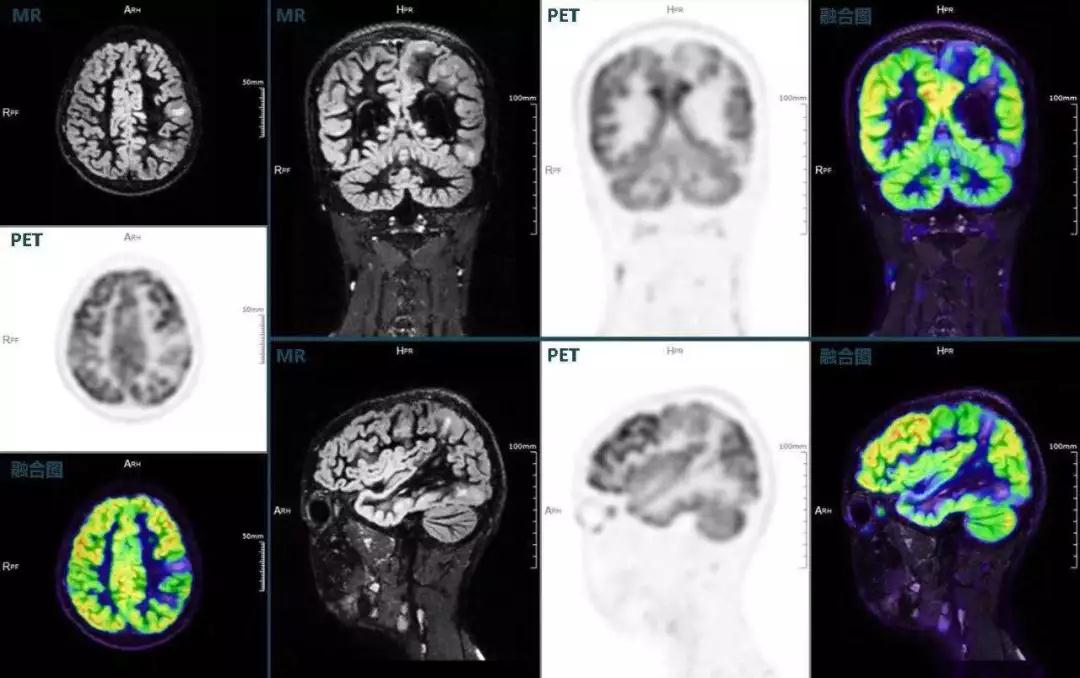

癲癇

不僅如此,聯(lián)影“時空一體”超清TOF PET/MR還搭載了大量可用于神經(jīng)疾病領域的高級應用,如DIR(Double Inversion Recovery雙反轉恢復)序列能夠清晰顯示大腦皮層的結構成像,對于皮層腫脹,膠質增生等癲癇的影像征象都能清楚呈現(xiàn);DTI(Diffusion Tensor Imaging彌散張量成像)高級應用能夠顯示細小的神經(jīng)纖維束缺損,以更加定量的形式為醫(yī)生提供一個全新的診斷維度,輔助醫(yī)生精準診斷。

(結節(jié)性硬化,MR DIR序列清晰顯示腦皮層病理改變,PET顯示了病灶區(qū)域FDG的低濃聚。PET/MR融合顯像同時提供了結構異常改變和功能變化的信息。)